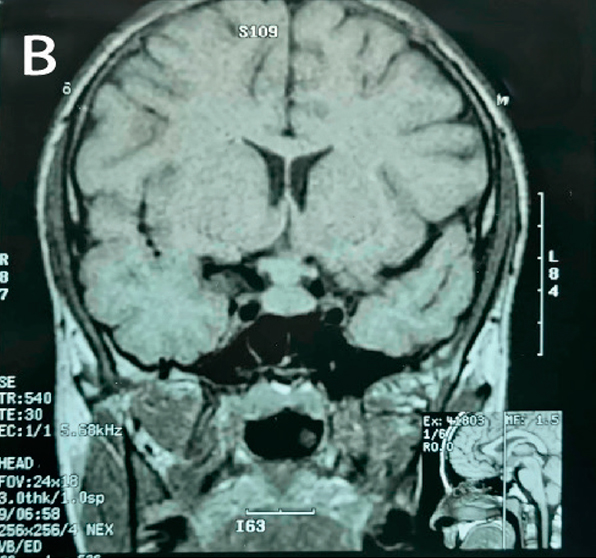

En la evolución se realiza RNM de control 2 años posteriores a primera RMN, que evidencia disminución del tamaño de la lesión tanto en el tallo hipofisario como de la hipófisis (Figura 2).

En lo endocrinológico, la afectación de la glándula hipófiisis se reporta en 5-50% de los pacientes con HCL, lo mas frecuente la deficiencia de arginina vasopresina en 50% de los casos7. Una minoría (5-20%) también presenta disfunción de hormonas de la adenohipófisis4,8,9. En la resonancia magnética nuclear (RMN) se puede encontrar a nivel de sistema nervioso central las siguientes manifestaciones: pérdida del punto brillante de la glándula pituitaria, engrosamiento del tallo pituitario >3 mm con realce, lesión masiva con isointensidad y realce homogéneo bajo imágenes potenciadas en T16.